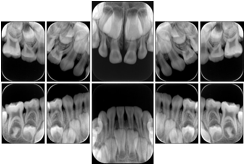

Intra-oral radiography typically involves acquisition of multiple images of various parts of the dentition. Many digital radiographic systems offer customized templates that are used for displaying the images in a study on the screen. These templates may also be referred to as mounts or view sets. The Structured Display Object represents a standard method of encoding and exchanging the layout and intended display of Structured Displays. A structured display object created in this manner could be stored with a study and exchanged with images to allow for complete reproduction of the original exam.

1. A patient visits a General Dentist where a Full Mouth Series Exam with 18 images is acquired. The dentist observes severe bone loss and refers the patient to a Periodontist. The 18 images from the Full Mouth Series along with a Structured Display are copied to a DICOM Interchange CD and sent with the patient to see the specialist. The Periodontist uses the CD to open the exam in his Dental Radiographic Software and consults via phone with the General Dentist. Both are able to observe the same exam showing the images on each user's display using the exact same layout.

Intra-oral Full Mouth Series Structured Display

Figure OO-1. Intra-oral Full Mouth Series Structured Display

In most standard cases, images are oriented in structured layouts. These structured displays are useful to be shared between providers for reference purposes.